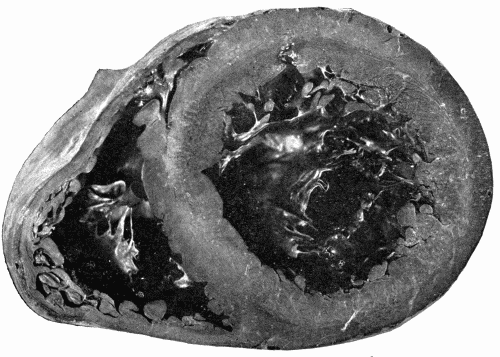

Fig. 4.—Arteriosclerosis of the arch of the aorta. Numerous calcified plaques,

thickening and curling of the aortic valves, giving rise to insufficiency of the aortic

valves. The aortic ring is rigid and not much dilated. (Milwaukee County Hospital.) Fig. 4.—Arteriosclerosis of the arch of the aorta. Numerous calcified plaques, thickening and curling of the aortic valves, giving rise to insufficiency of the aortic valves. The aortic ring is rigid and not much dilated. (Milwaukee County Hospital.)

Fig. 7.—Syphilitic aortitis of long standing. The aortic valves are curled and

thickened, the heart is enlarged and the cavity of the left ventricle is dilated. (Milwaukee

County Hospital.) Fig. 7.—Syphilitic aortitis of long standing. The aortic valves are curled and thickened, the heart is enlarged and the cavity of the left ventricle is dilated. (Milwaukee County Hospital.)